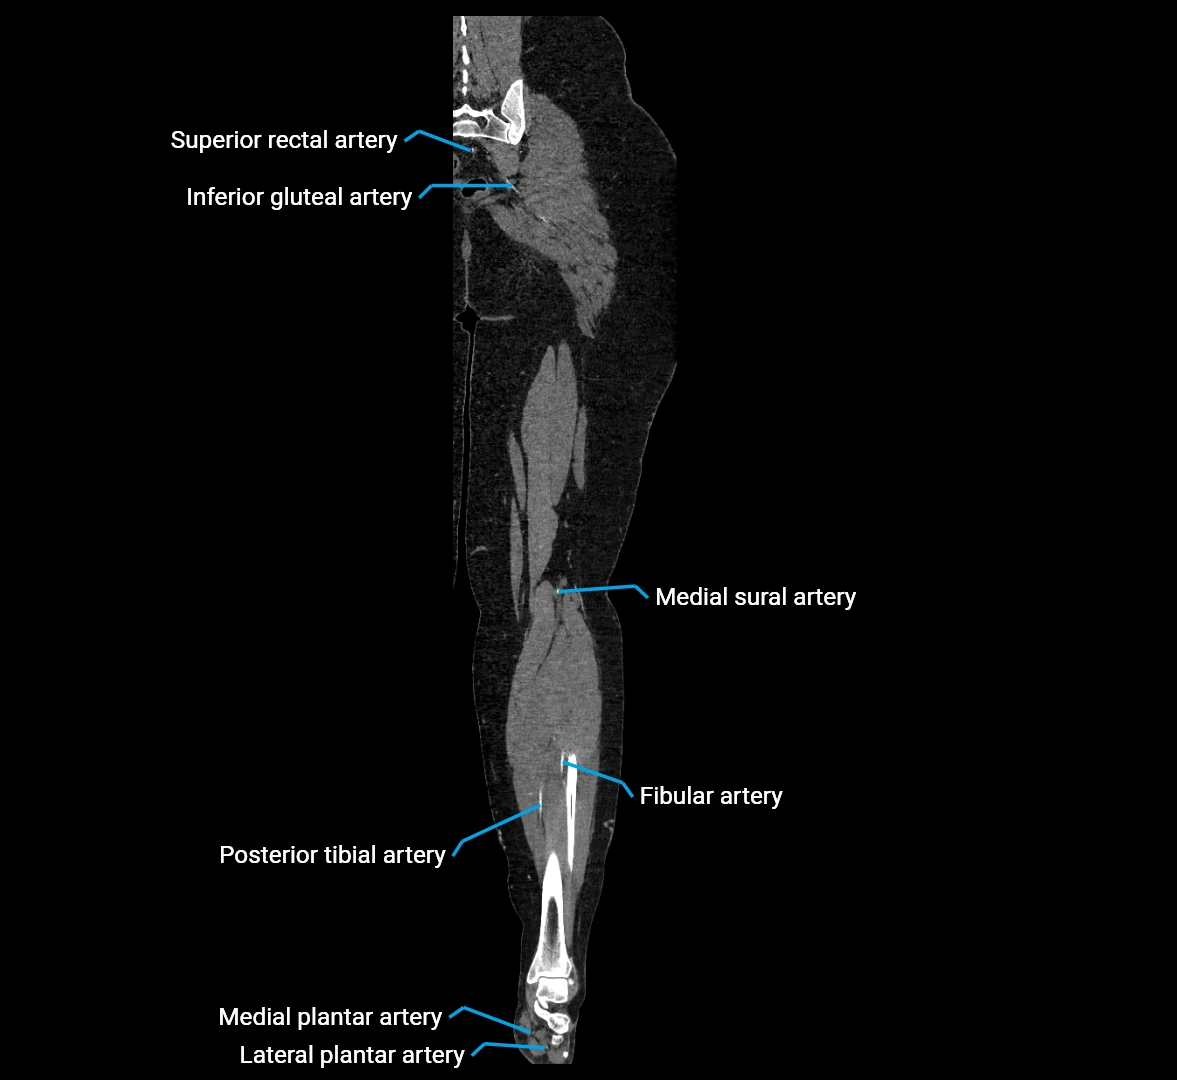

CT images

image

Contrast-enhanced CT (CTA):

• Gold standard for abdominal aortic imaging

• Provides excellent detail of lumen, wall, aneurysm, thrombus, and branch vessels

• Multiplanar and 3D reconstructions help in aneurysm measurement, stent graft planning, and dissection evaluation